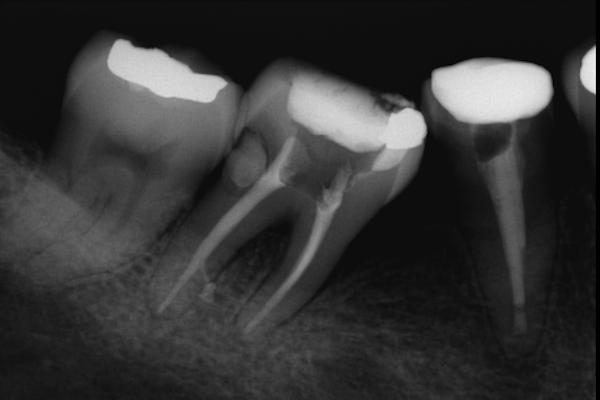

Endodoncia por caries en la raíz de la pieza dental

Paciente X de B años de edad, llega con amplia caries en la zona de a raíz. Se realiza endodoncia para salvarlo de una extracción. Al final se rehabilitó su pieza dental con una incrustación.

El paciente en su consulta de diagnóstico

El paciente feliz, al finalizar su tratamiento